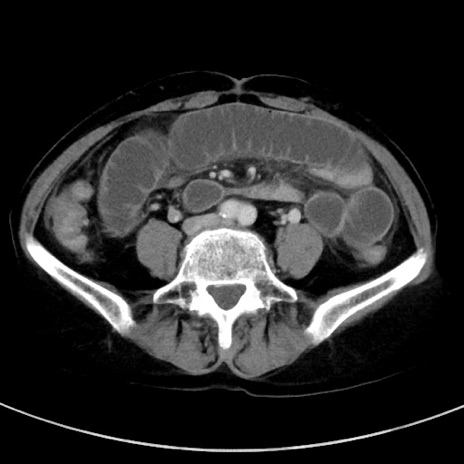

症例23(横断像)

【症例】70歳代女性

【主訴】下腹部痛・嘔吐

【現病歴】2日前より腹痛あり。昨日嘔吐あり。症状改善しないため来院。

【既往歴】胃GISTに対して胃部分切除後。

【身体所見】BT 37.1℃、BP 128/77mmHg、腹部:平坦・軟、下腹部に圧痛あり。

【データ】WBC 10200、CRP 0.31